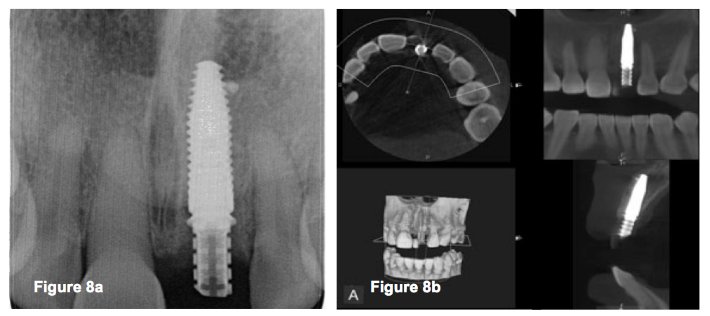

Straumann blt xray. Prophylaxis paste and cup 4. Bone level tapered implants blt refine. Implant blt the straumann bone level tapered implant comes in the materials roxolid with the slactive and sla surface or titanium with an sla surface a unified color code simplifies identification of instruments and im. X ray holder and film 2.

O 29 mm 1 o 33 mm 2 o 41 mm 2 o 48 mm. Straumannbone level tapered blt soft bone hard bone mandible in densifying mode make sure your osteotomy is 10 mm deeper than the actual implant final length. The straumann bone level tapered blt implant offers all the clinically proven features of the straumann bone level implant line plus the advantages of a tapered implant body. Implant blt straumann dental implant system.

In extreme hard bone utilize dac densify after cut protocol. Tissue level implants bone level implants. The shape surface and material combination are designed to deliver primary stability in all bone classes making the straumann bone level implant ideal for. Disposable saliva ejector and control pads 5.